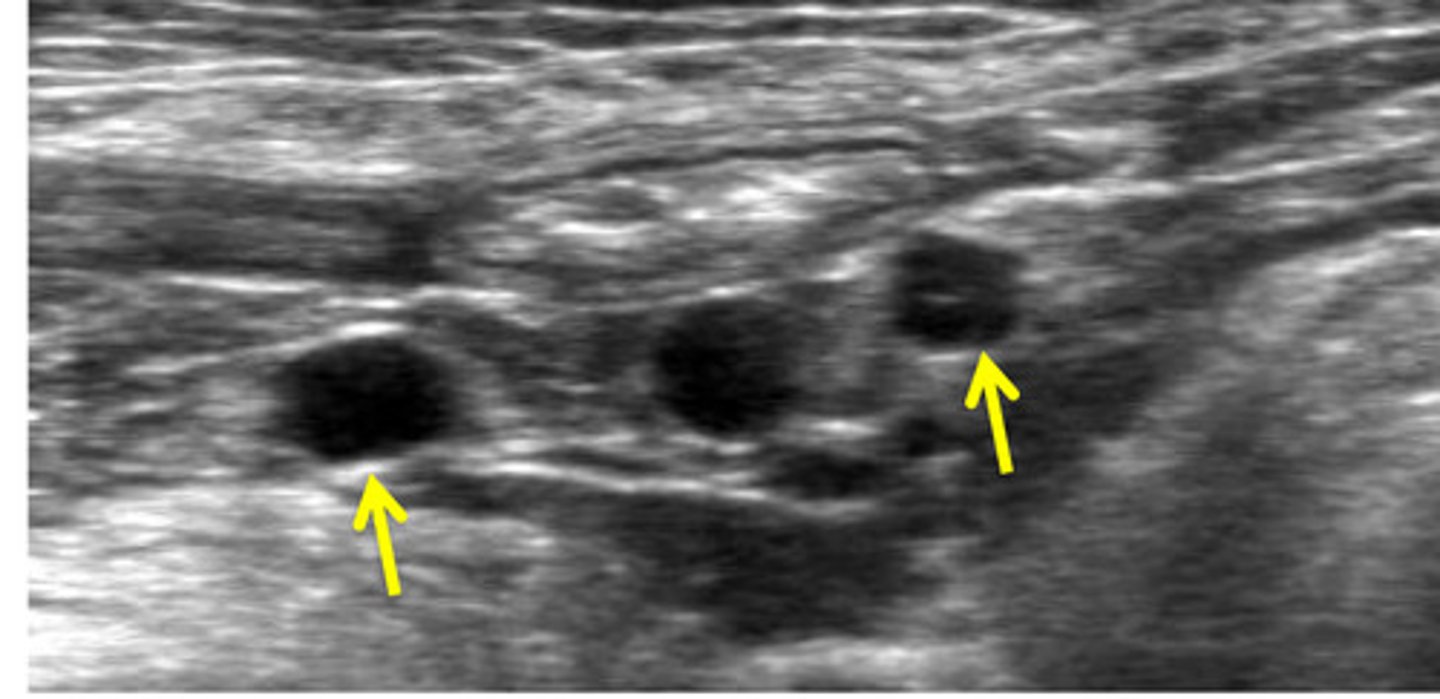

jejunal lns.

what are these lns.?

paired

the jejunal lns. are paired or unpaired?

cranial mesenteric

the jejunal lns. are 2 elongated structures on either side of the ____________ artery

jejunum, ileum and pancreas

what do the jejunal lymph nodes drain?